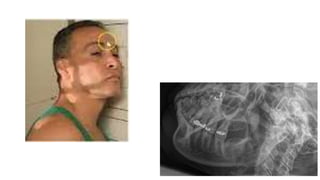

 Findings

 Xray views for mandible

 AP and lateral radiographs of the skull show a well defined lytic lesion involving

the left ramus of the mandible causing scalloping of the medial margin with

associated soft tissue swelling.

MANDIBLE XRAY

 Axiolateral oblique

 The patient is seated upright

 Give true lateral position

 Slightly extend the neck

 Tilt the head towards the detector

 Central ray 25-30 degree cephalad